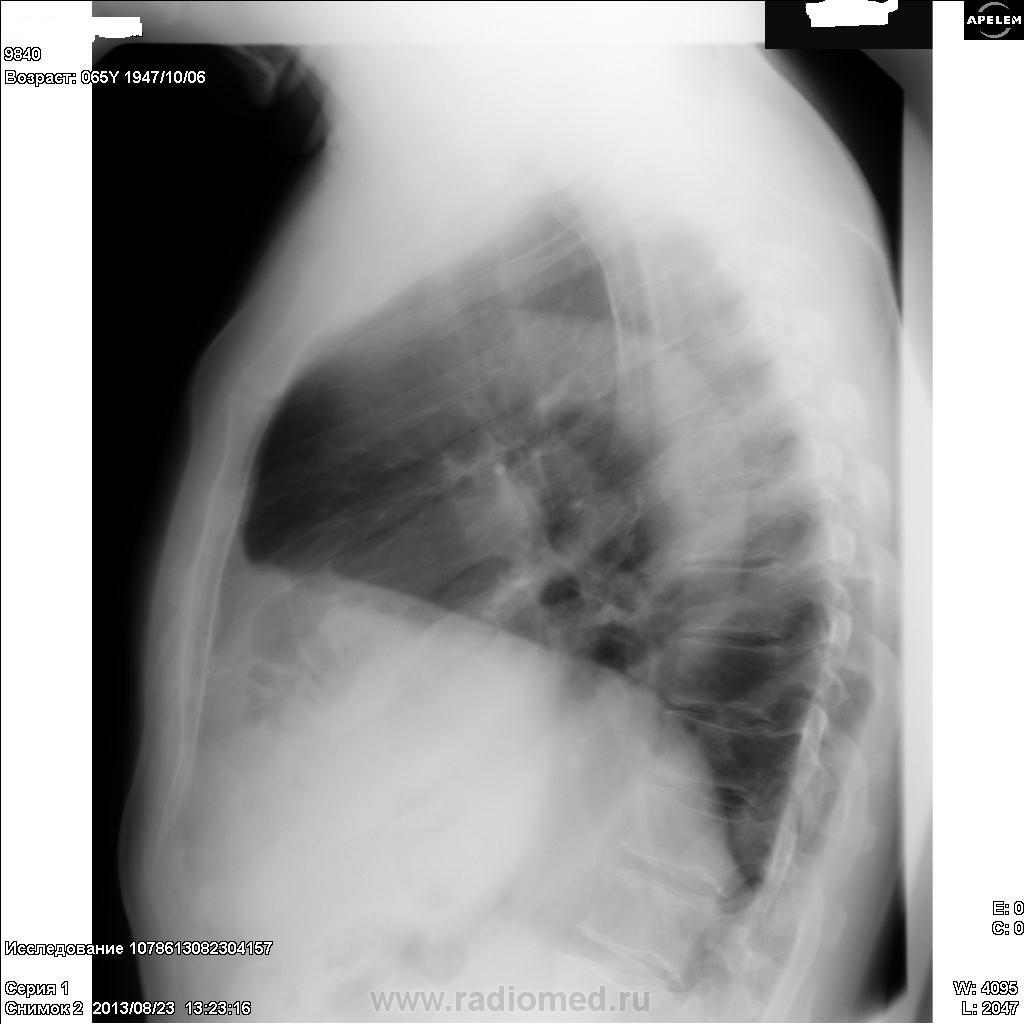

ХИЛАИДИТИ СИНДРОМ – интерпозиция печеночного угла толстой кишки между печенью и диафрагмой. Бывает постоянная (фиксация спайками) и перемежающаяся. Основные клинические проявления: чувство тяжести и боли в правом подреберье, запоры, частичная и даже полная кишечная непроходимость, уменьшение высоты печеночной тупости (если кишка содержит газ). Печеночная тупость может уменьшаться (или отсутствовать) также при эмфиземе легких, атрофическом циррозе печени и перфорации желудочно-кишечного тракта.

Хилаидити.

Это одно и то же. Ещё уважаемый коллега Nikolas, не указал, что интерпозиция толстой кишки может и никак не проявляться.